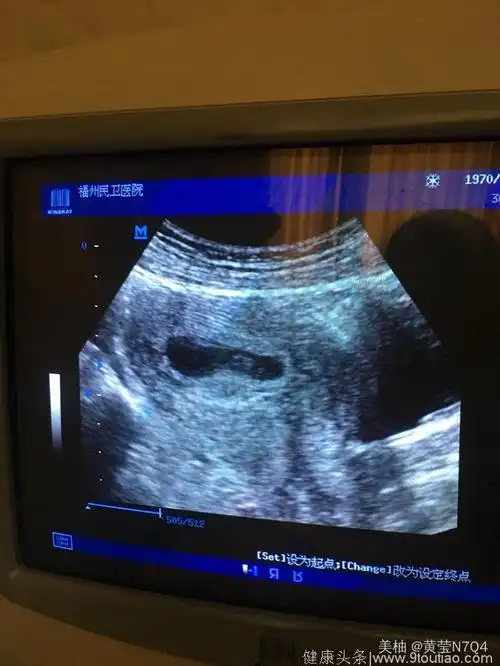

长孕囊和圆孕囊图片孕囊一定是男孩的图片